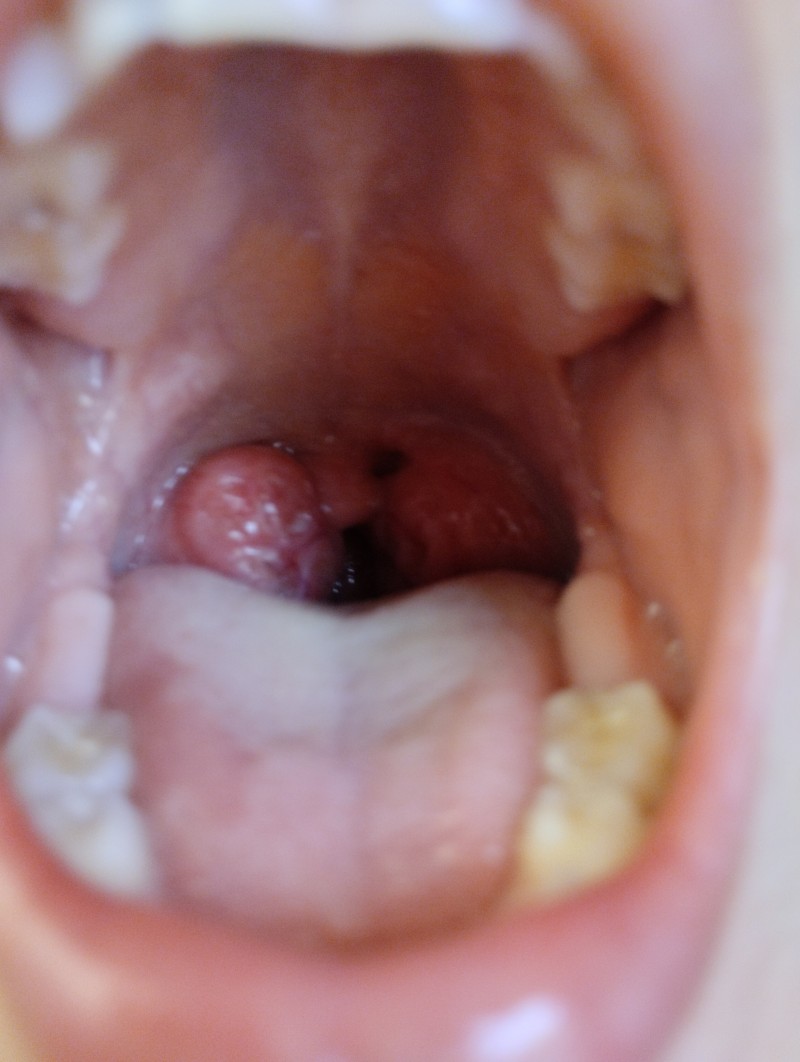

KKızım geçensene genız eti ameliyat olmuştu dünde bademcıklerını farkettım sizce çokmu büyük yaa haftaya randevu aldım bakalım inşallah amelıyat demez

image